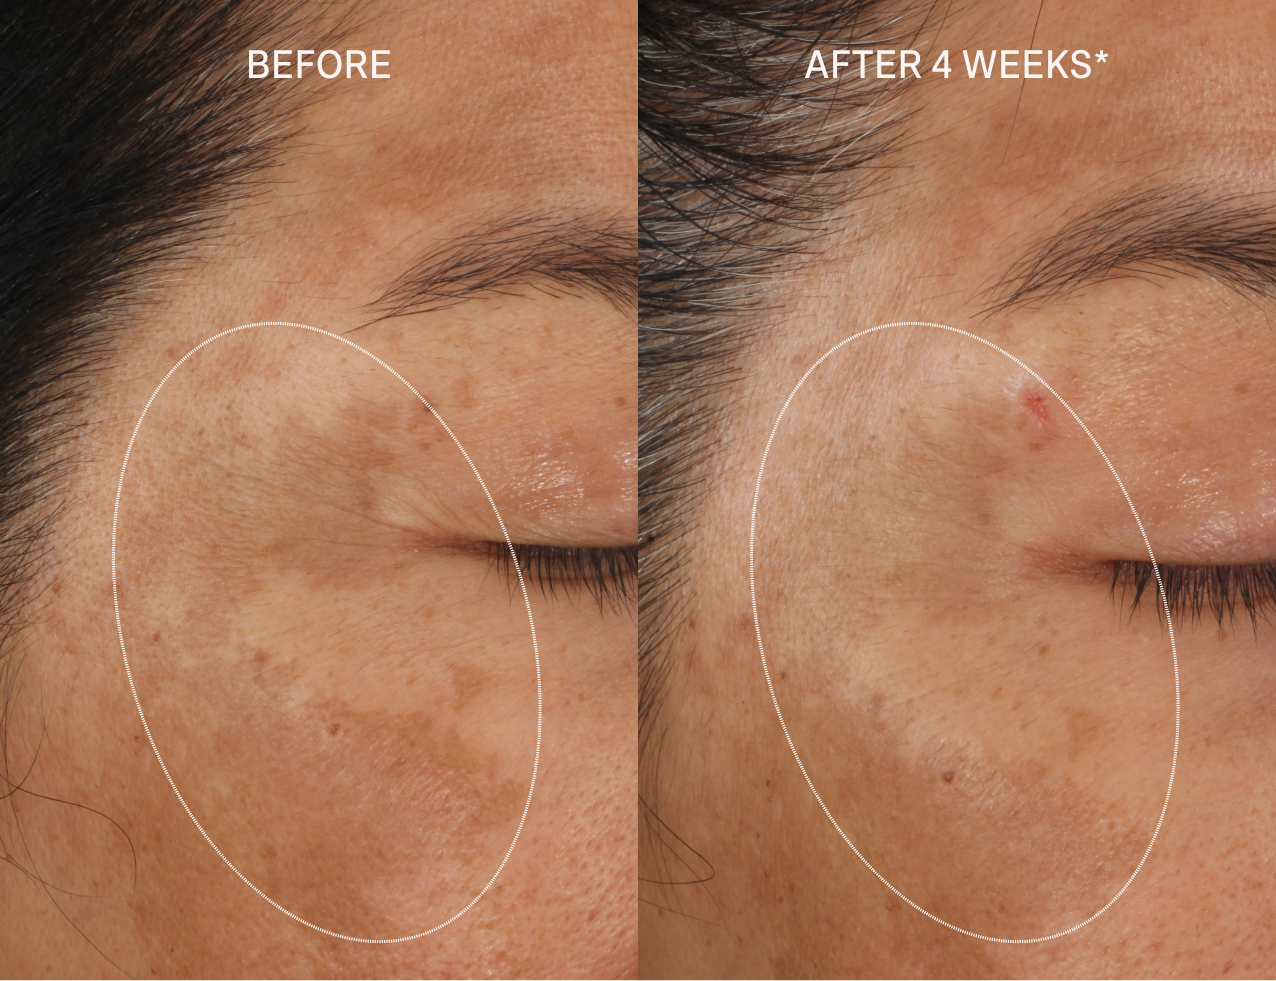

CLINICALLY PROVEN RESULTS

In just 4 weeks*:

- 100% of participants had a reduction in dark spots

- 100% saw brighter, smoother skin

- 100% said their skin tone looked more even

- 94% said their skin looked more youthful

Clinical Claims for Molecular Hero Serum

After 2 weeks*:

- 100% of participants had improvement in the appearance of dark spots

- 89% said their skin looked smoother

- 78% noticed brighter skin

After 4 weeks*:

- 100% had a reduction in the appearance of dark spots

- 100% saw brighter, smoother skin

- 100% had a visible improvement in lines and wrinkles

- 100% said their skin tone looked more even

- 94% said their skin looked more youthful

*Based on two clinical studies across 38 people using instrumentation, VISIA photography, expert grading, and consumer perception. Participants used Molecular Hero Serum twice daily.